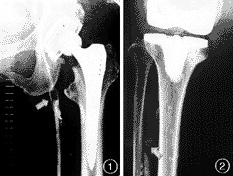

【摘要】目的 了解人工关节置换术后深静脉血栓的发生情况。方法 51例未行预防性抗凝治疗的人工关节置换患者于术后3~13天行双侧上行性静脉造影,分析调查术后深静脉血栓的发病情况。结果 人工关节置换术后深静脉血栓的总发生率为47.1%,全髋关节置换术后深静脉血栓的发生率为40.0%,全膝关节置换术后深静脉血栓的发生率为53.8%。未见症状性肺栓塞患者。结论 本组统计人工关节置换术后深静脉血栓的发生率和国外报道接近,这一结果应该引起人工关节外科医师的高度重视,并应针对存在高危因素的患者酌情给予适当的预防性治疗。

Abstract Objective Todetermine the incidence of deep venous thrombosis after total joint arthroplasty. Methods Fifty-one patients hadbilateral ascending venography between 3rd and 13th day after total joint replacement. Results The total incidence of deep venous thrombosis was 47.1% among 51 patients who had adequate venography, 40.0% occurred in total hipreplacement and 53.8% intotal knee replacement. No symptomatic pulmonary embolism was found. Conclusion The results indicate deep venous thrombosis after total joint arthroplasty is similar tothat reported in the foreign literature. This suggests that prophylactic treatment isreasonable in patients with high risk of deep veinous thrombosis.